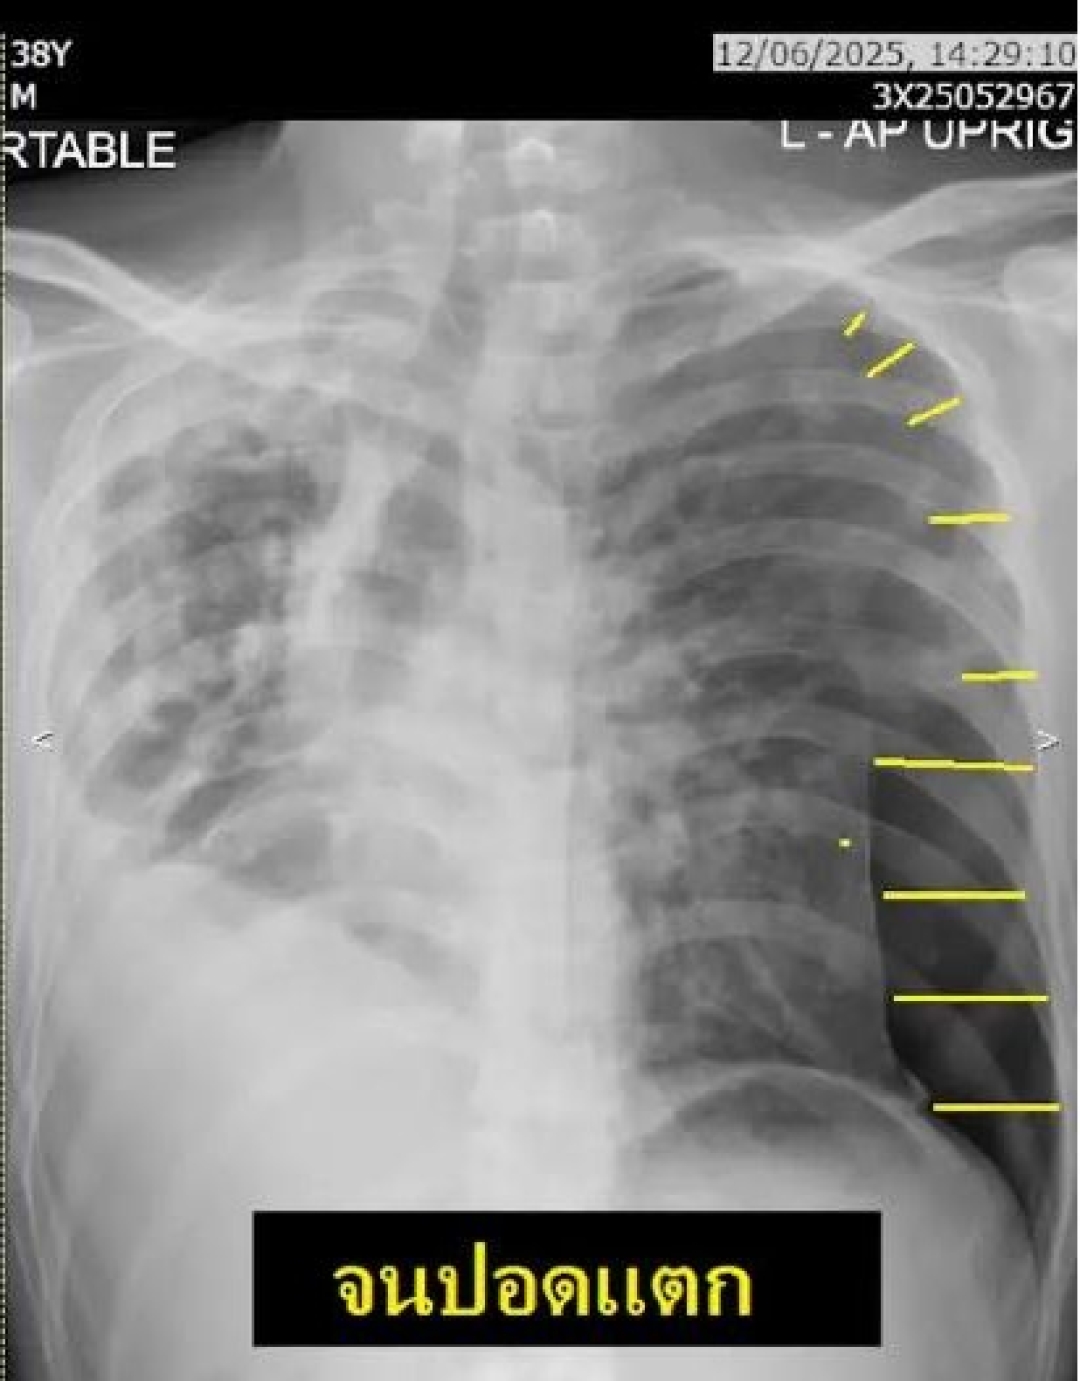

ผ่านไปหนึ่งเดือน น้องมาด้วยเรื่องปอดแตกด้านซ้าย หายใจล้มเหลว (เส้นสีเหลืองแสดงให้เห็นปริมาตรปอดที่ถูกยุบ) ญาติแจ้งว่าตรวจพบมีสารเสพติดในห้องนอน

จากภาพที่หนึ่งจะเห็นว่า(ลูกศร) ปอดด้านขวามีฝ้าขาวเต็ม ทั่วปอด มีการดึงรั้งให้หลอดลมเอียง มีโพรงเต็มปอด